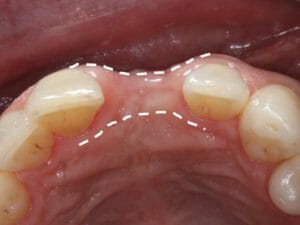

Ridge Preservation

Once a tooth is removed the bone shrinks to help the body efficiently use its resources. It is important to preserve the bone ridge before this happens. The most effective time for this is during a tooth extraction. During this procedure, the body normally forms a blood clot in a large empty space. After the wound contracts during healing, the bony ridge has become much smaller, possibly too small for an implant. When we perform grafting, wound contraction is prevented, leaving the bone ridge in its original shape and ready for an implant. If you'd like to learn more about bone grafting for dental implants, Jacksonville & surrounding areas contact us today at one of our four convenient locations.